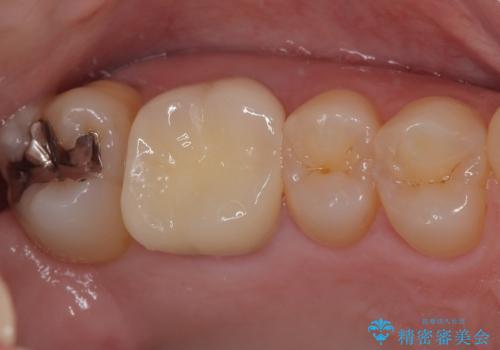

- 以前他院で治療を行った前歯の被せものが欠けてしまい、きれいなセラミックにしたいと来院された患者様です。

人工物のような印象が強くあまり自然とは言えない状態でした。

また被せものと土台の間に隙間があり、適合もよくない状態でした。

根管治療のやり直しは希望されなかったため、土台のやり替えと、より自然なオールセラミッククラウンへのやり替えを行いました。